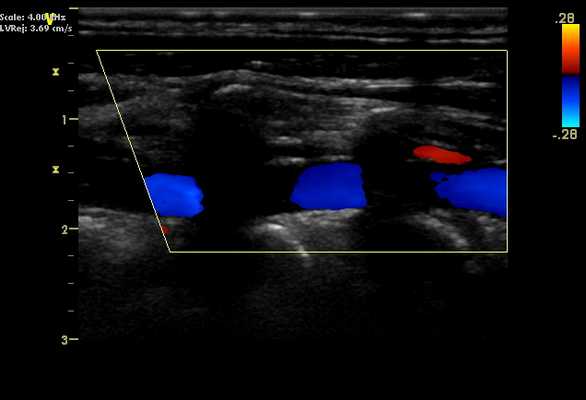

Позвоночная артерия на УЗИ. Позвоночную артерию визуализируют, помещая датчик в промежуток между трахеей и грудинно-ключично-сосцевидной мышцей, при этом голова пациента находится в боковом положении. Ультразвуковой луч направляется перпендикулярно ОCA. Общая сонная артерия располагается прямо по экрану, а ультразвуковой луч наклоняют в боковом направлении до тех пор, пока не будут визуализированы поперечные отростки шейного отдела позвоночника. Здесь будет видна позвоночная артерия, проходящая через поперечные отверстия шейного отдела позвоночника, на ультразвуковом изображении в виде прерывистых теней. Позвоночная вена при ультразвуковом сканировании проходит впереди артерии.